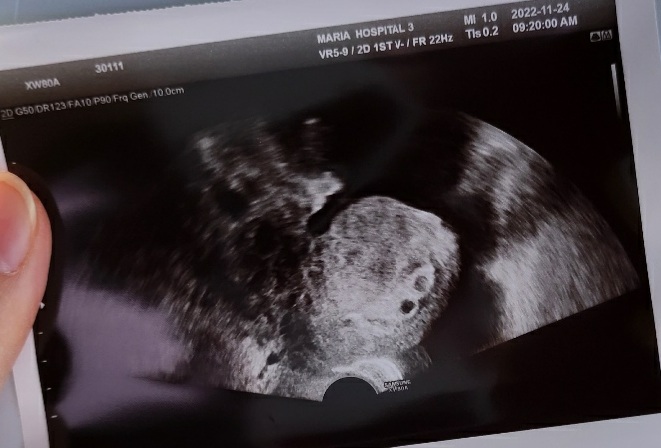

초음파 보니 아직은 아주 작은 우리 아가들의 심장이 콩닥콩닥 열심히 뛰는 모습이 보였다.

작은 우리 아가들 열심히 잘 자라주고 있구나 하는 생각에 우리 아가들이 기특하기까지 했다.